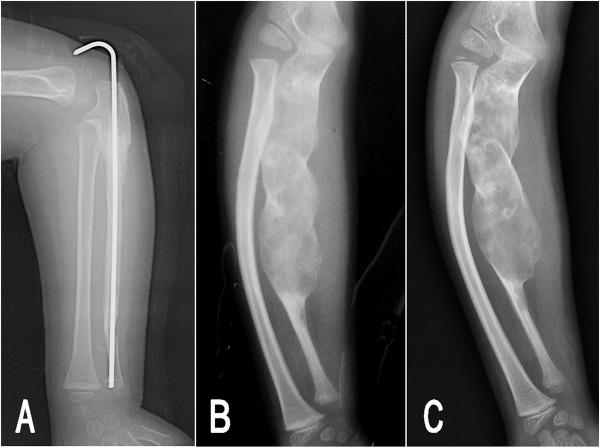

The surgical treatment of fibrous dysplasia remains a challenge for the pediatric orthopedist because of its high recurrence rate. Although a few successful treatments have been reported by using en bloc resection and bone graft in adults, this has not been reproduced in children. In this report, the authors present two children (2.5 and 6 years old) with monostotic expansile fibrous dysplasia involving the ulna and fibula, respectively, who underwent en bloc resection and autograft to replace the involved bones. Good bone union and functional recovery were obtained postoperatively. However, during a follow-up period of 8 and 5 years, respectively, the lesions recurred completely, and the deformities remained progressing over time. En bloc resection and bone graft cannot prevent recurrence in skeletally immature patients with monostotic expansile fibrous dysplasia, and cannot alter for the natural history of the disease. A combination of other management should be considered in children with fibrous dysplasia.

由于纤维结构不良的高复发率,其外科治疗对小儿骨科医生来说仍是一项挑战。尽管已有报道称在成人中采用整块切除和骨移植取得了一些成功的治疗案例,但在儿童中尚未得到重现。在本报告中,作者介绍了两名分别为2.5岁和6岁的儿童,他们分别患有累及尺骨和腓骨的单骨型膨胀性纤维结构不良,均接受了整块切除和自体骨移植以替换受累骨骼。术后获得了良好的骨愈合和功能恢复。然而,在分别为期8年和5年的随访期内,病变完全复发,畸形随时间持续进展。对于骨骼未成熟的单骨型膨胀性纤维结构不良患者,整块切除和骨移植无法预防复发,也无法改变疾病的自然病程。对于患有纤维结构不良的儿童,应考虑联合其他治疗方法。